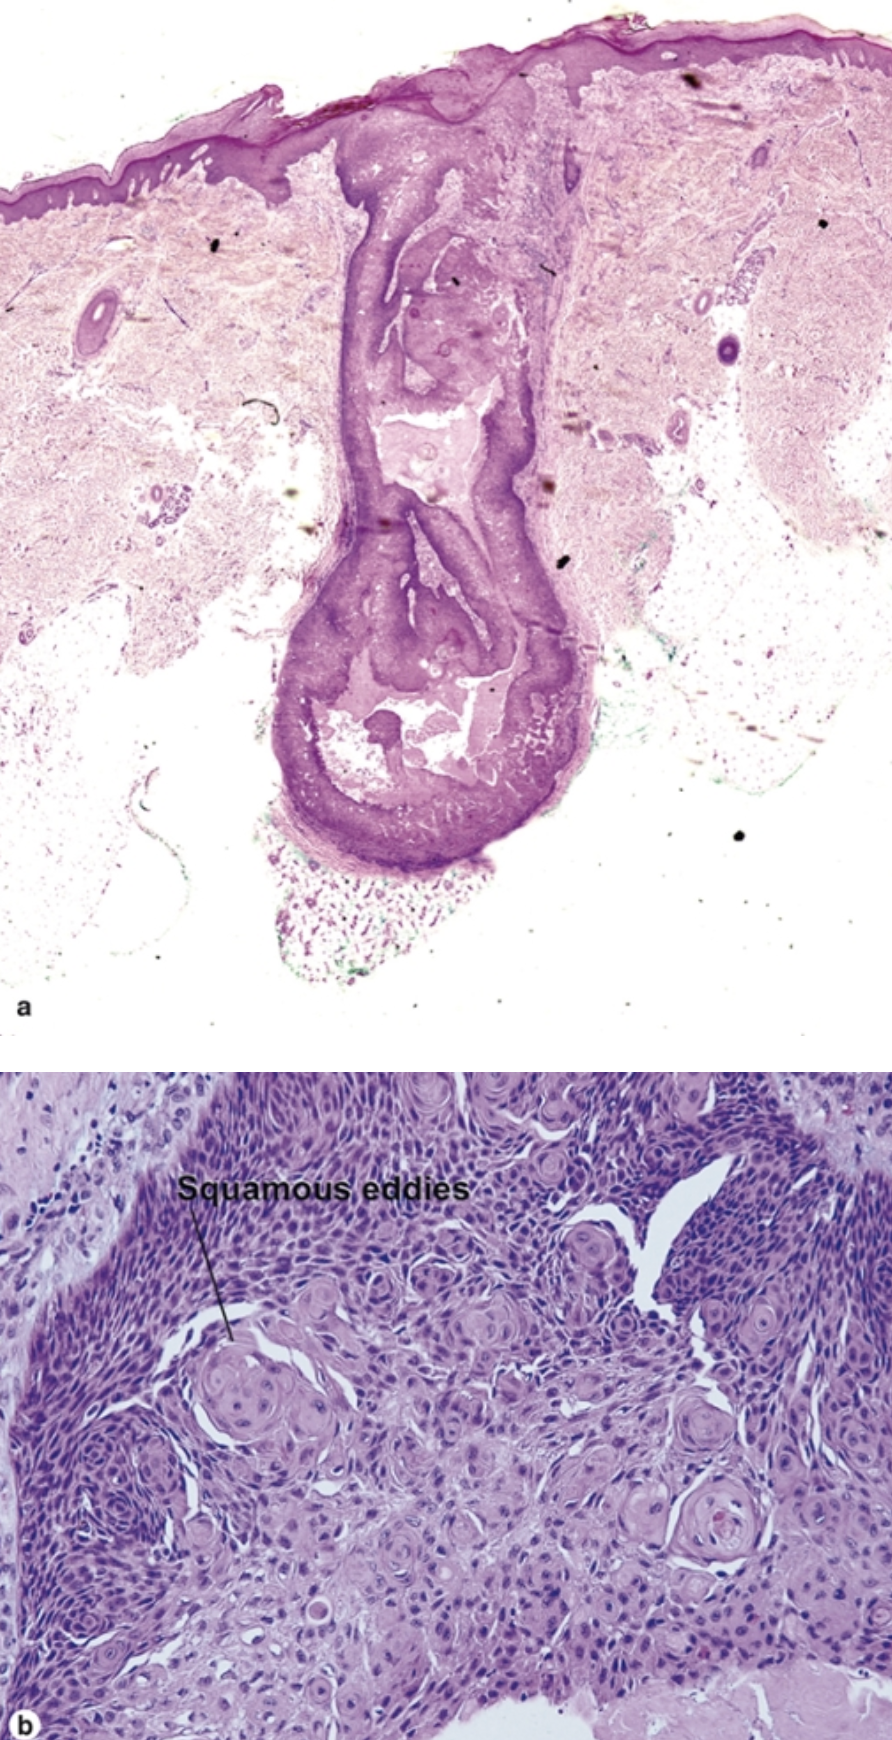

What are the features of a warty dyskeratoma?

What are the histologic findings of a warty dyskeratoma? (at least 3)